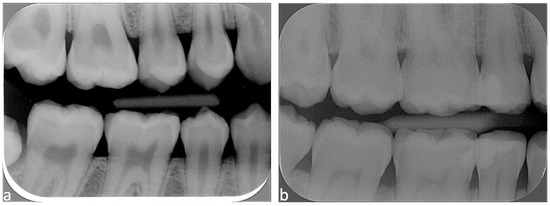

| Centering the cone with or without rectangular collimator | Image outline Tooth fully visible | Complete image outline; borders not cut No truncated image | Incomplete image outline; image cut without consequences on diagnosis | Incomplete image outline, image cut, with consequence on diagnosis |

| Centering of the digital plate | Ratio of maxillary and mandibular quadrants (visibility of teeth and alveolar crest at vertical level) | 50–50% ratio: image well centered vertically (maxillary and mandibular teeth each cover 50% of the image) | 40–60% ratio: image moderately centered vertically (one quadrant covers more than half of the image, alveolar bone visible on both quadrants) | Image not vertically centered (one quadrant covers more than 60% of the image, alveolar bone of opposite quadrant not visible) |

| Distal contact points (between canines and the 2nd lower molars) | 4 distal contact points are visible | 3 distal contact points are visible | <3 distal contact points are visible | |

| Correct bite on the film-holder | -- | Yes Upper and lower quadrants in contact with film-holder | No One quadrant without contact with film-holder | |

| Superposition of enamel (horizontal angulation) | Superposition of enamel on the contact points | Superposition <1/3 of enamel width | Superposition between 1/3 and 2/3 of enamel width | Superposition >2/3 of enamel width |